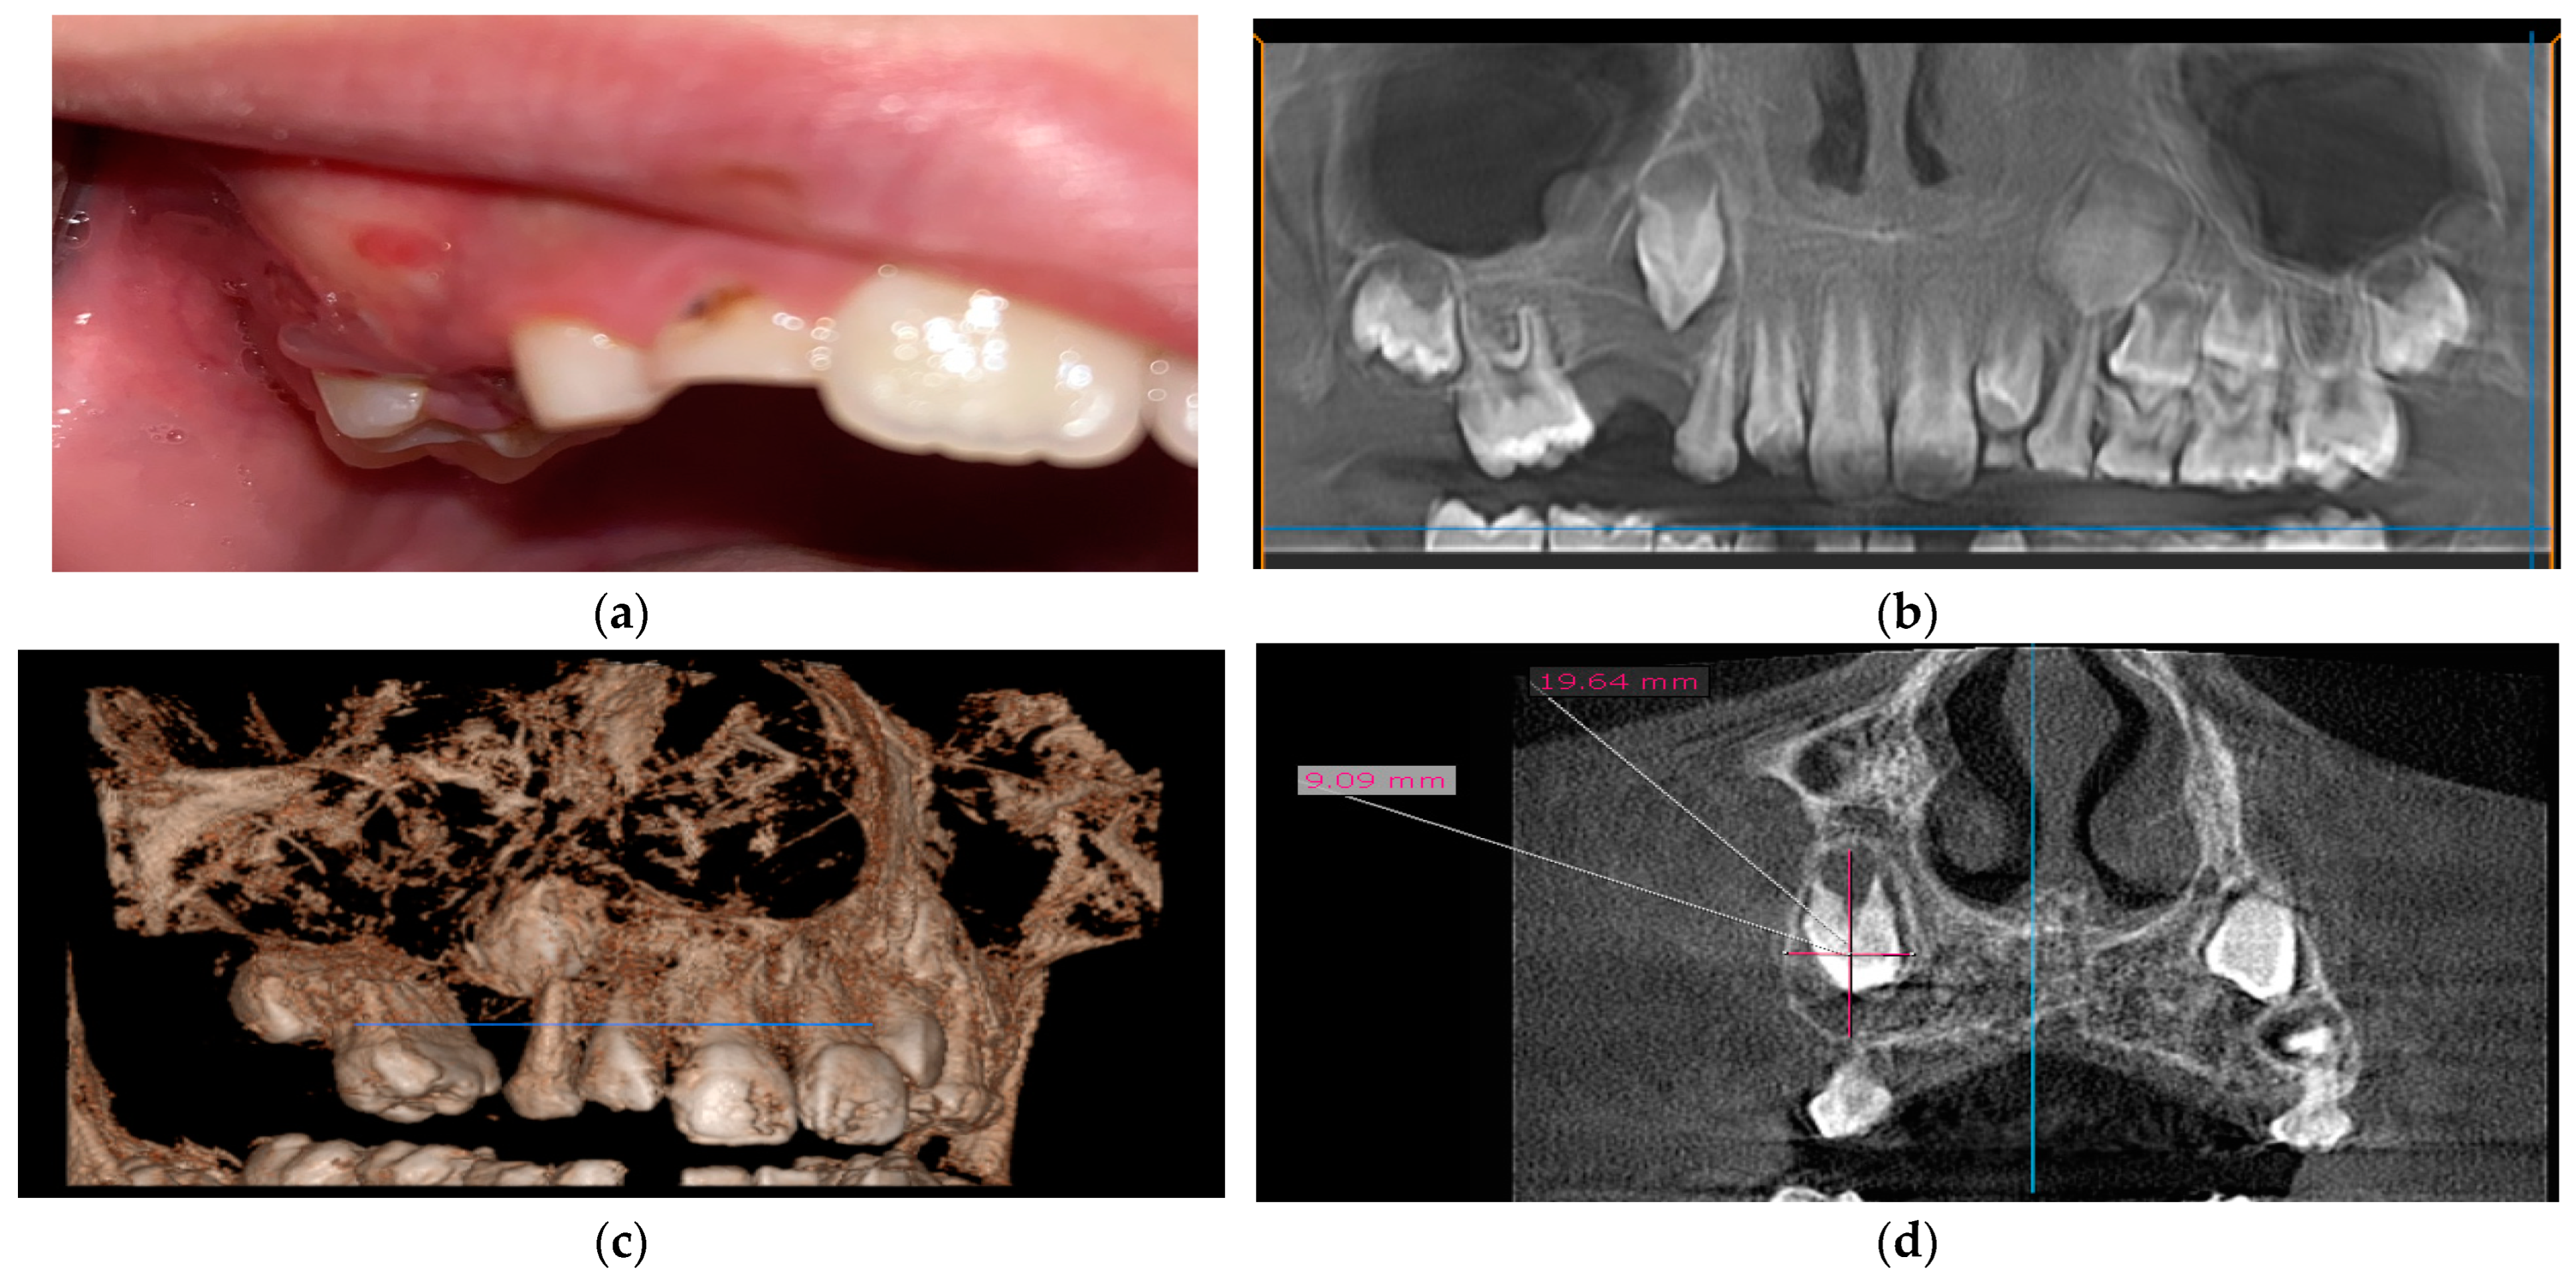

2.2.1. Case 1

2.2.2. Case 2

2.2.3. Case 3